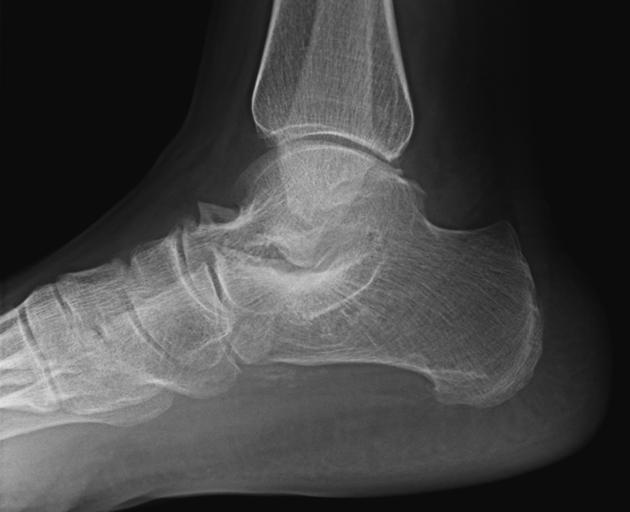

Diagnosis?

Common presentation?

Talocalcaneal coalition- talar beaking with absence of the middle facet of the subtalar joint. 2nd most common type of coalition (after calcaneo-navicular), can be osseous, fibrous, or cartilaginous.

May present with peroneal spastic flatfoot.